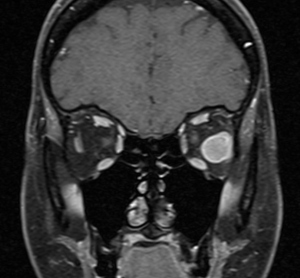

High-resolution orbital imaging is essential for the evaluation of suspected orbital GCTs. Both Computed Tomography (CT) and Magnetic Resonance Imaging (MRI) offer complementary information, with MRI generally favored for lesion characterization. The majority of infraorbital GCTs appear as well circumscribed, round lesions.[23] On CT, they appear as well-defined, homogeneous soft tissue masses that are isodense or mildly hyperdense to muscle.[8] Adjacent bony changes are uncommon, a finding better appreciated on CT.[23] On contrast-enhanced CT, GCTs typically show moderate, homogeneous enhancement.[23] On MRI, Orbital GCTs are generally isointense to gray matter on T1-weighted imaging and hypointense to isointense on T2-weighted sequences, a pattern that differs from most benign orbital tumors, which are typically T2-hyperintense.[8][23] MRI with gadolinium demosntrates slight to strong enhancement with avid peripheral enhancement (see image 1 and 2). [4][8] Diffusion weighted imaging generally does not show diffusion restriction.[23] ADC measurements have been investigated for use in differentiating benign from malignant lesions, however there is not a specific value which supports a diagnosis of GCT. [23]